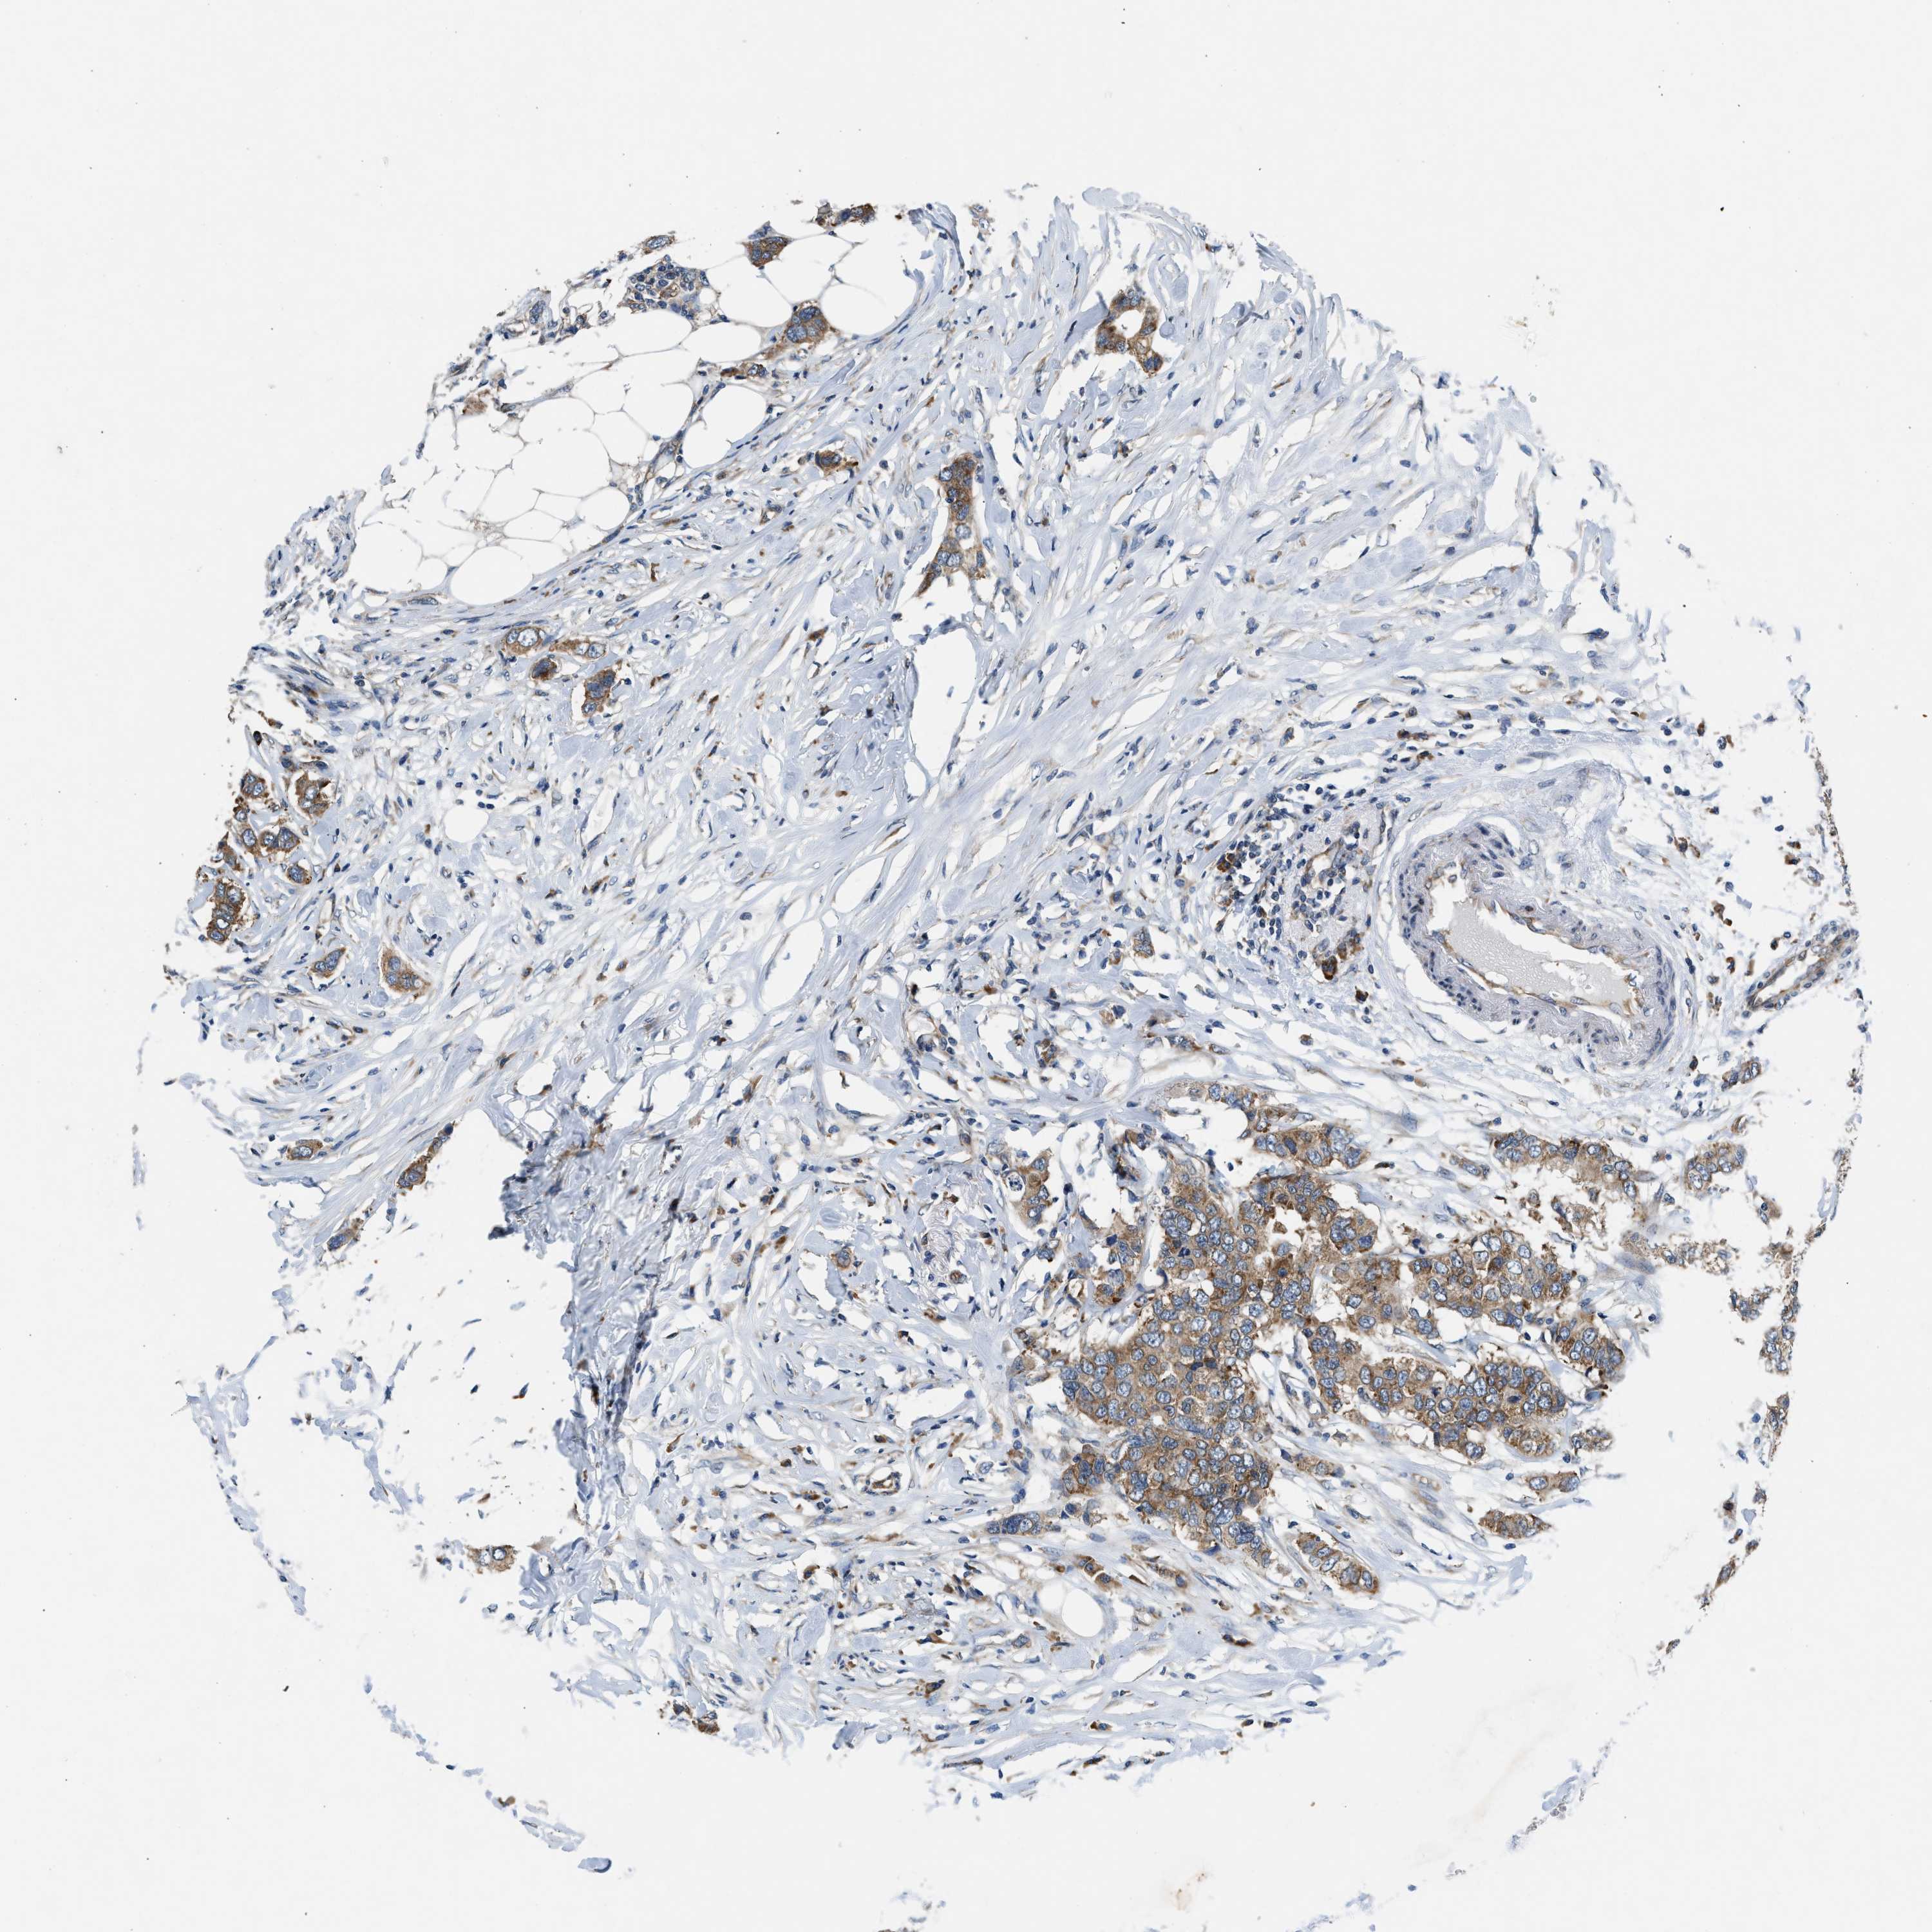

BRCA TCGA BRCA VALIDATION PROTEIN EXPRESSION

Breast cancer

Human cancer